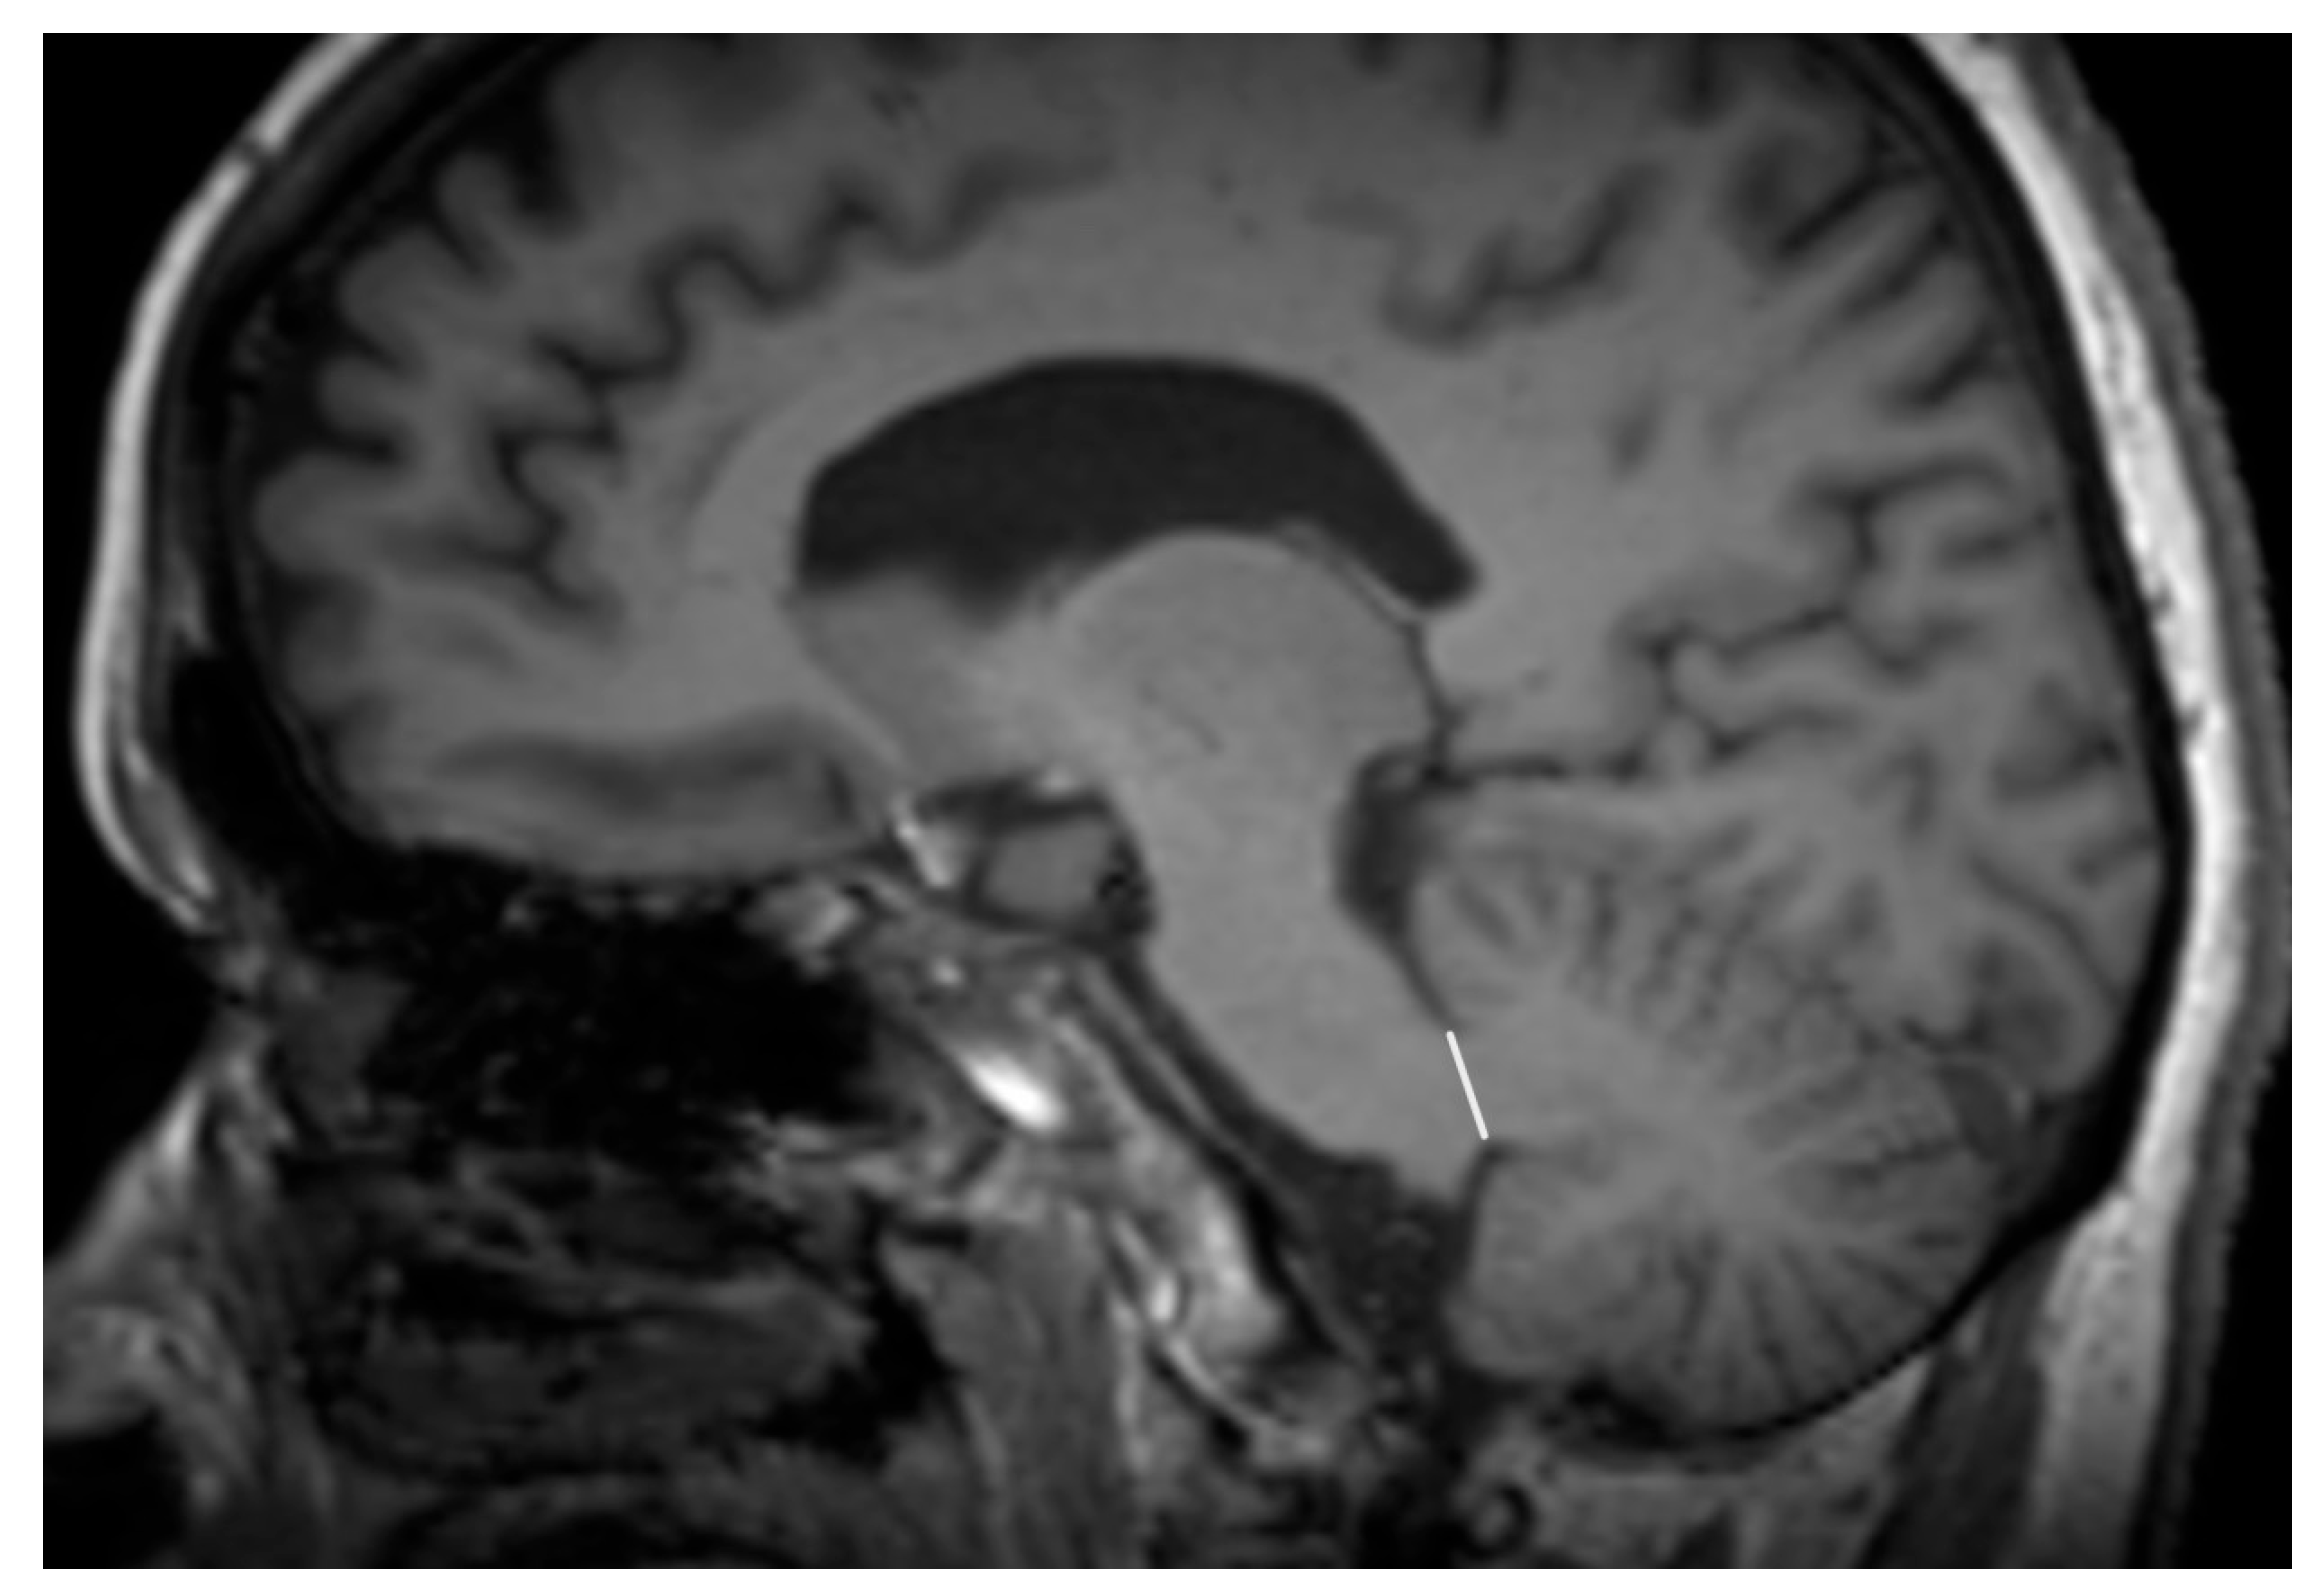

- Spiegel, C.; Marotta, C.; Bertram, K.; Vivash, L.; Harding, I.H. Brainstem and cerebellar radiological findings in progressive supranuclear palsy. Brain Commun. 2025, 7, fcaf051. [Google Scholar] [CrossRef]

- Watanabe, H.; Yoshida, M.; Naganawa, S.; Sobue, G. The diagnosis of neurodegenerative disorders based on clinical and pathological findings using an MRI approach. Rinsho Shinkeigaku 2011, 51, 863–864. [Google Scholar] [CrossRef][Green Version]

- Longoni, G.; Agosta, F.; Kostić, V.S.; Stojković, T.; Pagani, E.; Stošić-Opinćal, T.; Filippi, M. MRI measurements of brainstem structures in patients with Richardson’s syndrome, progressive supranuclear palsy-parkinsonism, and Parkinson’s disease. Mov. Disord. 2011, 26, 247–255. [Google Scholar] [CrossRef] [PubMed]

- Hwang, M.; Yang, H.; Kim, Y.; Youn, J.; Park, J.; Huh, Y.E.; Kim, H.T.; Cho, J.W. Differential Progression of Midbrain Atrophy in Parkinsonism: Longitudinal MRI Study. Neurodegener. Dis. 2017, 17, 31–37. [Google Scholar] [CrossRef] [PubMed]

- Grijalva, R.M.; Pham, N.T.T.; Huang, Q.; Martin, P.R.; Ali, F.; Clark, H.M.; Duffy, J.R.; Utianski, R.L.; Botha, H.; Machulda, M.M.; et al. Brainstem Biomarkers of Clinical Variant and Pathology in Progressive Supranuclear Palsy. Mov. Disord. 2022, 37, 702–712. [Google Scholar] [CrossRef]